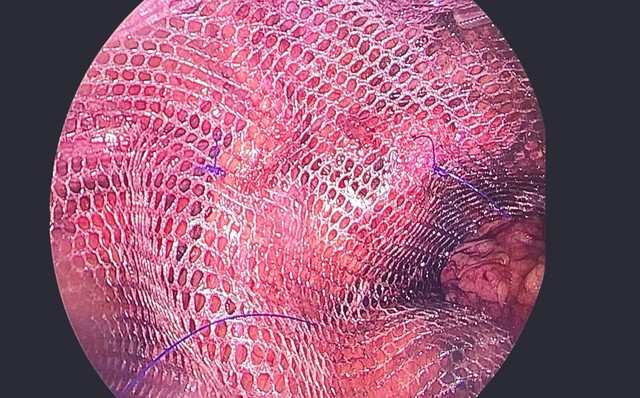

Tấm lưới nhân tạo được đặt che phủ vùng bẹn

ẢNH: BVCC

Sau khi thăm khám và đánh giá toàn diện, ông D. được các bác sĩ khoa Ngoại Tổng hợp, Bệnh viện đa khoa quốc tế Nam Sài Gòn tư vấn điều trị bằng phẫu thuật nội soi đặt lưới hoàn toàn trước phúc mạc (TEP) - một kỹ thuật hiện đại trong điều trị thoát vị bẹn.

Ca phẫu thuật do ThS-BS-CKI Nguyễn Huy Hoàng phối hợp cùng ThS-BS Phạm Trường Minh và ê-kíp gây mê hồi sức thực hiện. Các bác sĩ tiến hành bóc tách, xử lý túi thoát vị và đặt lưới 15x15 cm che phủ toàn bộ vùng bẹn yếu nhằm đảm bảo thành bụng được củng cố vững chắc. Ca mổ diễn ra thuận lợi sau hơn 1 giờ đồng hồ.